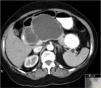

A 74-year-old woman was referred for further evaluation of a large pancreatic cystic lesion. She presented with abdominal discomfort, without weight loss, anorexia or history of pancreatitis or abdominal trauma. Physical examination revealed a large epigastric mass. A contrast-enhanced computed tomography (CT) showed a huge, well-defined, multiloculated cyst of 12cm in greatest dimension arising from the pancreatic body, with multiple wall calcifications, without typical imaging features of a particular pancreatic cystic neoplasm (Fig. 1). Endoscopic ultrasound (EUS) showed a multilocular cyst with a larger cyst (120mm×70mm) and a peripheral microcystic component (Fig. 2). EUS-guided fine-needle aspiration of 7mL of serous cystic fluid was performed from the largest cyst under prophylactic IV antibiotics. The sample had no malignant or mucus-producing cells and CEA (<2.5ng/mL) and amylase (41U/L) were within the reference values, making a serous cystadenoma the most likely diagnosis. Due to persistent epigastric discomfort, a distal pancreatectomy and splenectomy was performed (Fig. 3). Macroscopic examination of the resected specimen showed a combination of large cysts with several small cysts. On microscopy, the cysts were lined with a single layer of cuboidal epithelial cells with clear cytoplasm, PAS positive (Fig. 4). Histopathological examination confirmed the diagnosis of a pancreatic serous oligocystic adenoma.